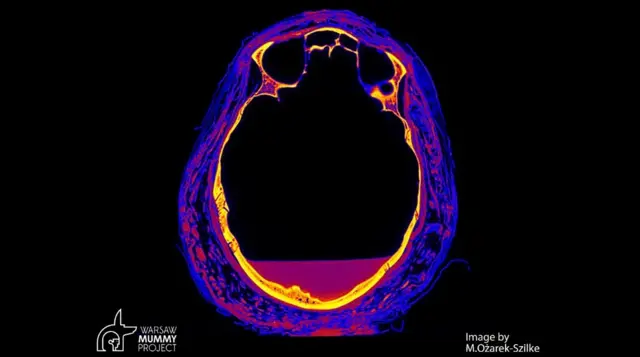

ล่าสุดมีการค้นพบเพิ่มเติมว่า สตรีปริศนาผู้นี้อาจเสียชีวิตด้วยโรคมะเร็งหลังโพรงจมูก ซึ่งเป็นโรคที่เนื้อร้ายจะแพร่กระจายตัวไปในช่องปาก โพรงจมูก และหลอดลม โดยในกรณีของมัมมี่ร่างนี้พบรอยโรคปรากฏเป็นรูโหว่ความกว้าง 7 มิลลิเมตร ที่บริเวณด้านหลังเบ้าตาข้างซ้าย

ดร. มาร์ซีนา โอซาเร็ก-ซิลเก ผู้นำทีมวิจัยจากมหาวิทยาลัยวอร์ซอบอกว่า ผลการตรวจสอบด้วยซีทีสแกนกับกะโหลกศีรษะของสตรีปริศนา พบว่ามีรูโหว่ที่น่าจะเกิดจากเนื้องอกหรือบาดแผลบางอย่าง เบียดกระดูกเบ้าตาบางส่วนให้แยกออกเป็นช่องว่าง แต่อาการนี้ก็อาจเกิดจากซีสต์ (cyst) หรือโรคโลหิตจางที่ทำให้มีรอยพรุนในกระดูกเบ้าตา ซึ่งเป็นอาการที่พบบ่อยในหญิงมีครรภ์ก็เป็นได้

อย่างไรก็ตาม ดร. โอซาเร็ก-ซิลเก แสดงความมั่นใจว่า รอยโรคดังกล่าวรวมทั้งความผิดปกติของรูปทรงกระดูกที่พบเพิ่มเติมบริเวณขากรรไกร โพรงจมูก และไซนัส (sinus) ชี้ว่าเป็นอาการของโรคมะเร็งอย่างแน่นอน ซึ่งน่าจะเป็นสาเหตุการเสียชีวิตหลักของสตรีปริศนา นอกเหนือไปจากความผิดปกติในการตั้งครรภ์